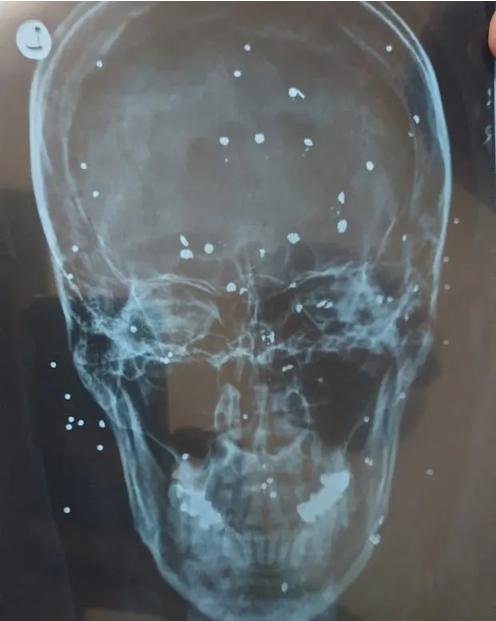

Medicii și asistentele, care îi tratează pe protestatari în secret pentru a evita arestarea, au spus că au observat pentru prima dată această practică după ce au văzut că tot mai multe femei soseau cu răni diferite față de bărbați ale căror răni, cel mai frecvent, erau în picioare, fese și spate. În timp ce o întrerupere a internetului a ascuns o mare parte a represiunii sângeroase asupra protestatarilor, fotografiile furnizate de medici pentru The Guardian au arătat răni cumplite pe tot corpul de la alicele pe care forțele de securitate le-au tras asupra oamenilor de la mică distanță. Unele dintre fotografii arată oameni cu zeci de bile mici înfipte adânc în carnea lor.

Un medic din provincia centrală Isfahan a spus că el crede că autoritățile vizează bărbați și femei în moduri diferite „pentru că au vrut să distrugă frumusețea acestor femei”. „Am tratat o femeie de 20 de ani, care a fost împușcată în organele genitale de două alice. Alte zece alice erau înfipte în interiorul coapsei. Aceste 10 alice au fost îndepărtate cu ușurință, dar cele două au fost o provocare, deoarece erau înfipte între uretră și deschiderea vaginală”, a spus medicul.

Foarte mulți protestatari au fost împiușcați de către forțele de ordine chiar și în ochi, sute de fete suferind de răni foarte garve la nivelul feței și al craniului.